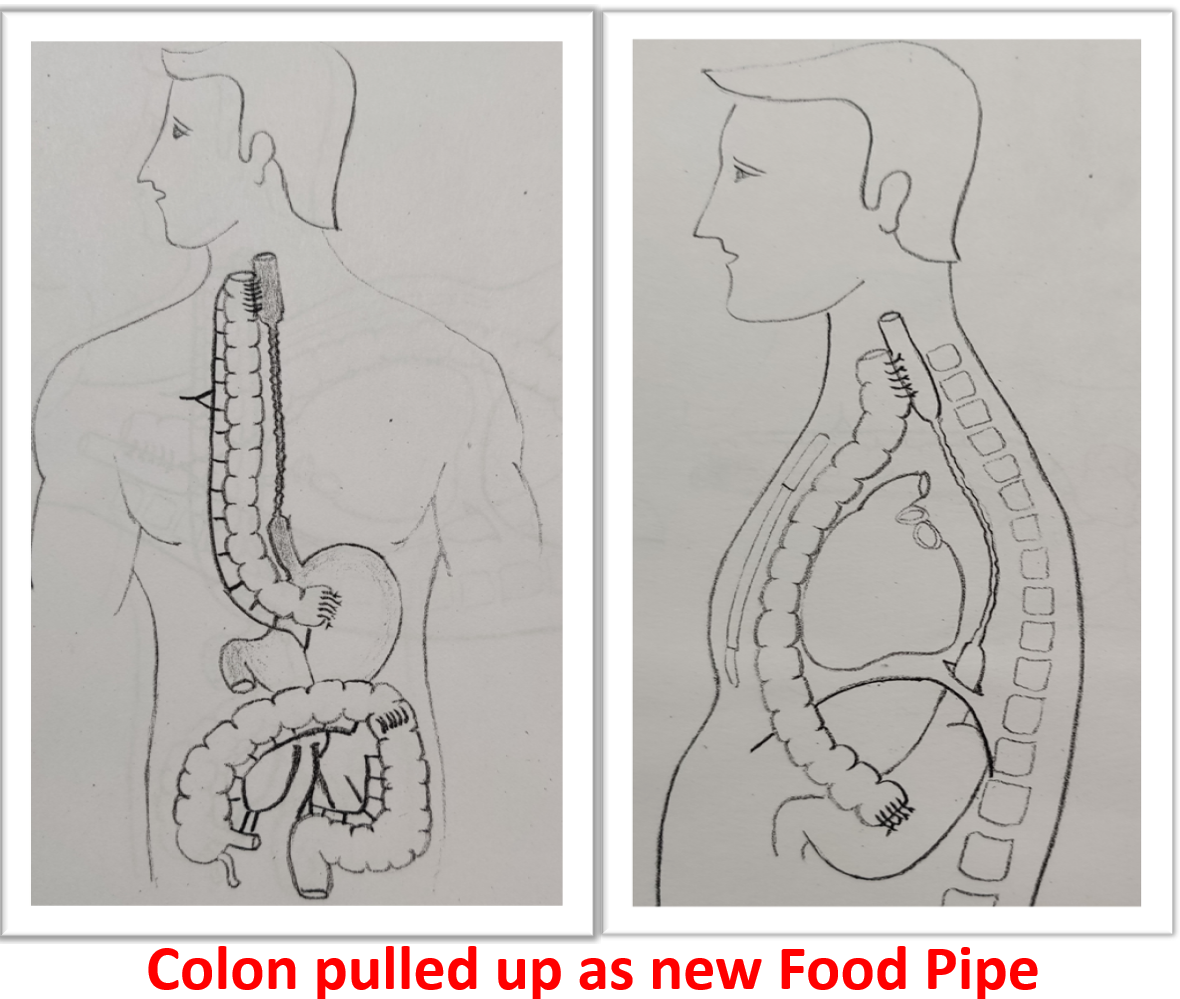

The treatment initially is to dilate the stricture with endoscope to restore eating which might be successful in some. Failing endoscopic dilatation or stricture which has ruptured during dilation need surgical replacement. Surgical replacement has evolved from using artificial pipes to bodies own organs suitable to restore the food pipe. The surgical principle is to identify the healthy upper part of esophagus which is in the neck, leave behind or remove the scarred esophagus, prepare the conduit (stomach tube, colon, jejunum) for replacement, transport it from abdomen to the neck under the chest bone (sternum) and join it to healthy esophagus in neck (Fig- 2/2p/3). The entire procedure involves three major compartments of human body, lasts from 4 to 8 hours, more than a week to recover from surgery and with known procedure related morbidity and mortality if not performed in a specialized centre. Patient are allowed to sip liquids from firs day to resume to normal diet may take a week but eventually they “EAT”